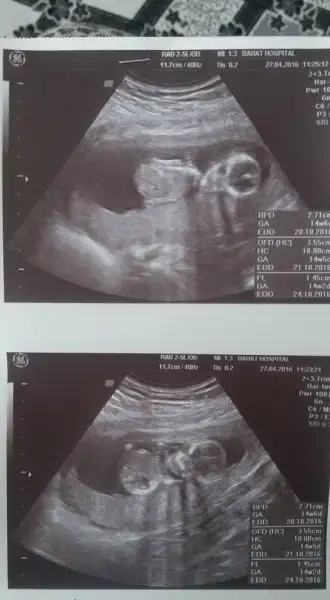

image.webp